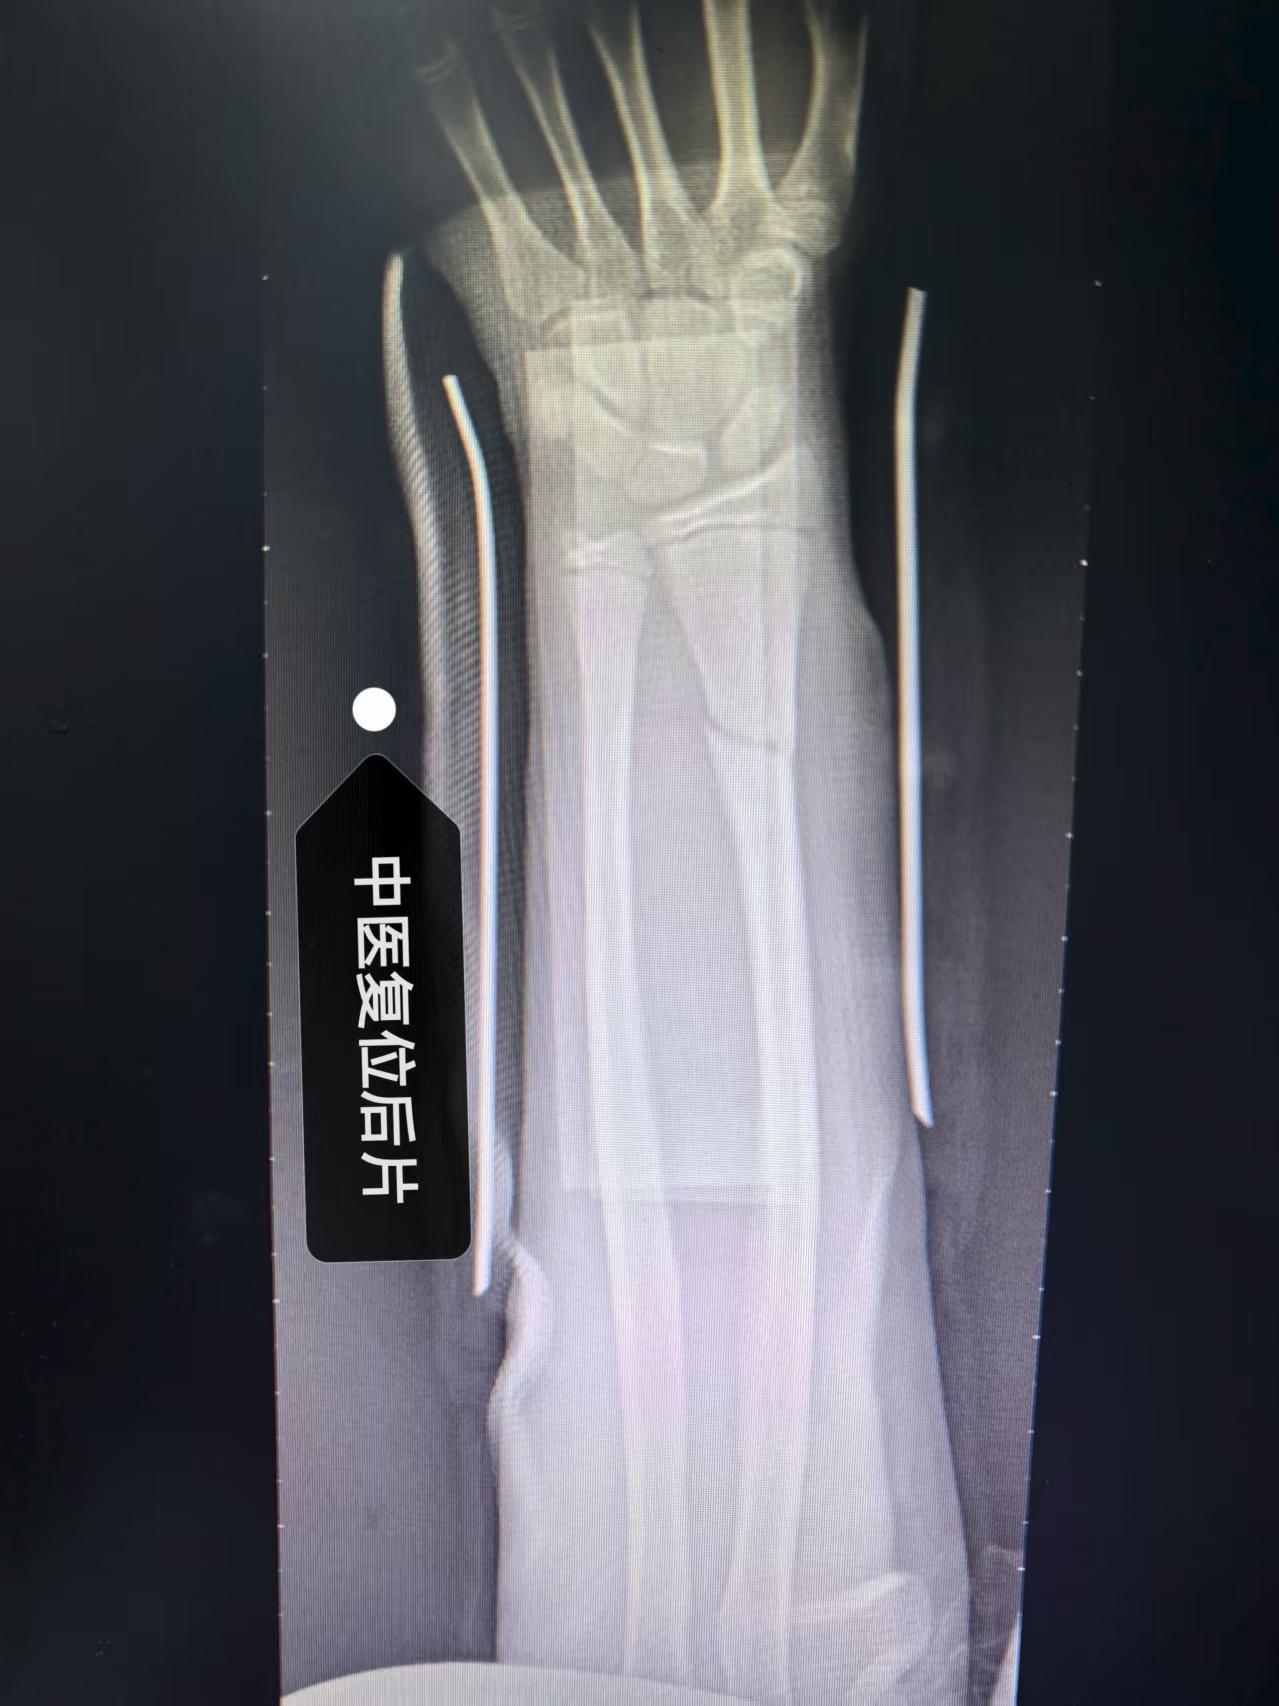

(这二张DR片,是经我院骨科运用传统中医手法复位加夹板外固定后即刻照片,疗效满意)